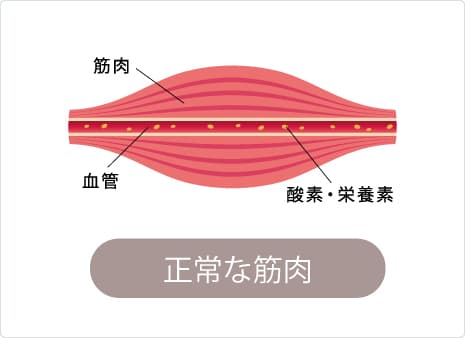

筋肉は血液から酸素やエネルギーをもらい正常に動きます。しかし、同じ姿勢や同じ動作を続ける事で筋肉に負担がかかり血流不足となりしびれが引き起こされます。

しびれの無い正常な筋肉というのは下図のように、血管から酸素や栄養素が運ばれ柔軟性のある状態です。

しかし、しびれがある筋肉は、血流不足により必要なエネルギーが筋肉に運ばれず筋肉がSOSを出している状態です。

この状態が続き負担がかかり続けると、筋肉は次第に硬くなり、皆さんが感じられる【コリ】となります。この筋肉のコリ・しこりのことを医学用語で【トリガーポイント】といいます。